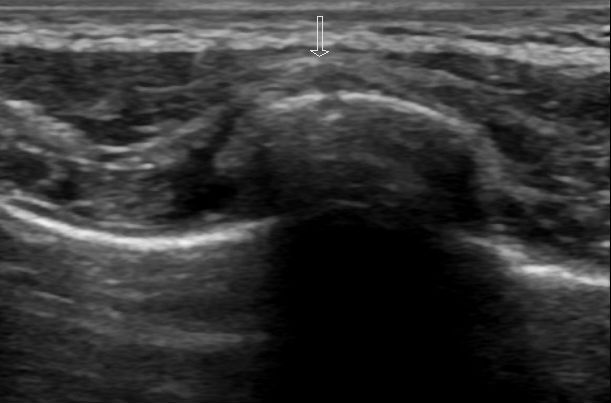

Figure 3:

Longitudinal view demonstrating a cortical break with overlying crescent shaped hematoma of the same rib fracture as figures 1 and 2.